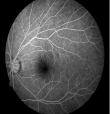

正常眼底造影